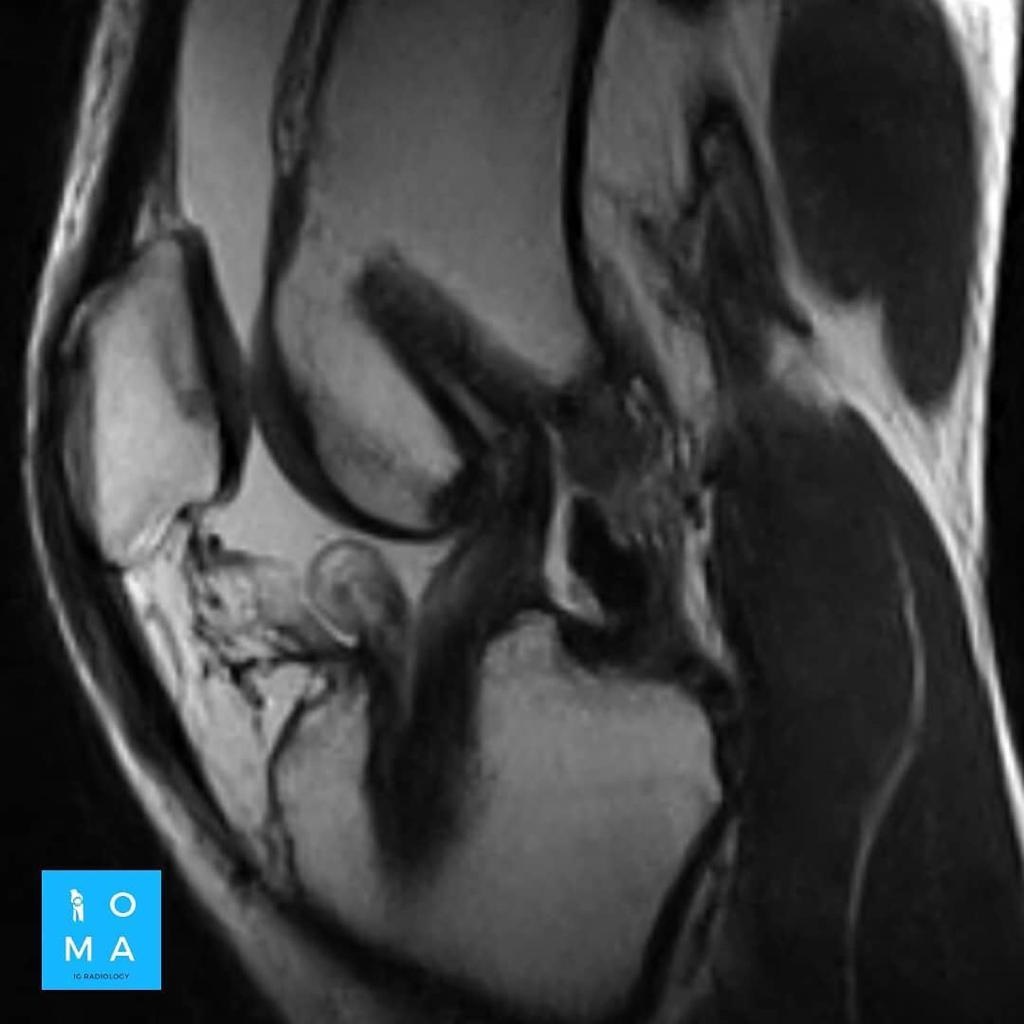

Se presenta caso de paciente de la 3a década, que en su embarazo se diagnostica con sospecha de adenoma y posterior al embarazo se realiza estudio de control contrastado para su mejor diferenciación.

En la evaluación con medio de contraste, se evalúa la relación arterial y de las venas, esto puede servir para buscar la arteria central relacionada con la hiperplasia nodular focal o bien, para evaluar la relación con las estructuras vasculares que son muy importantes para el planeamiento quirúrgico .

en este caso, aún cuando los hallazgos son atípicos tanto para hiperplasia nodular focal como para adenoma, nos inclinamos hacia el diagnóstico de adenoma debido a los antecedentes de la paciente, el tamaño de la lesión, el área de sangrado, el contenido de grasa.